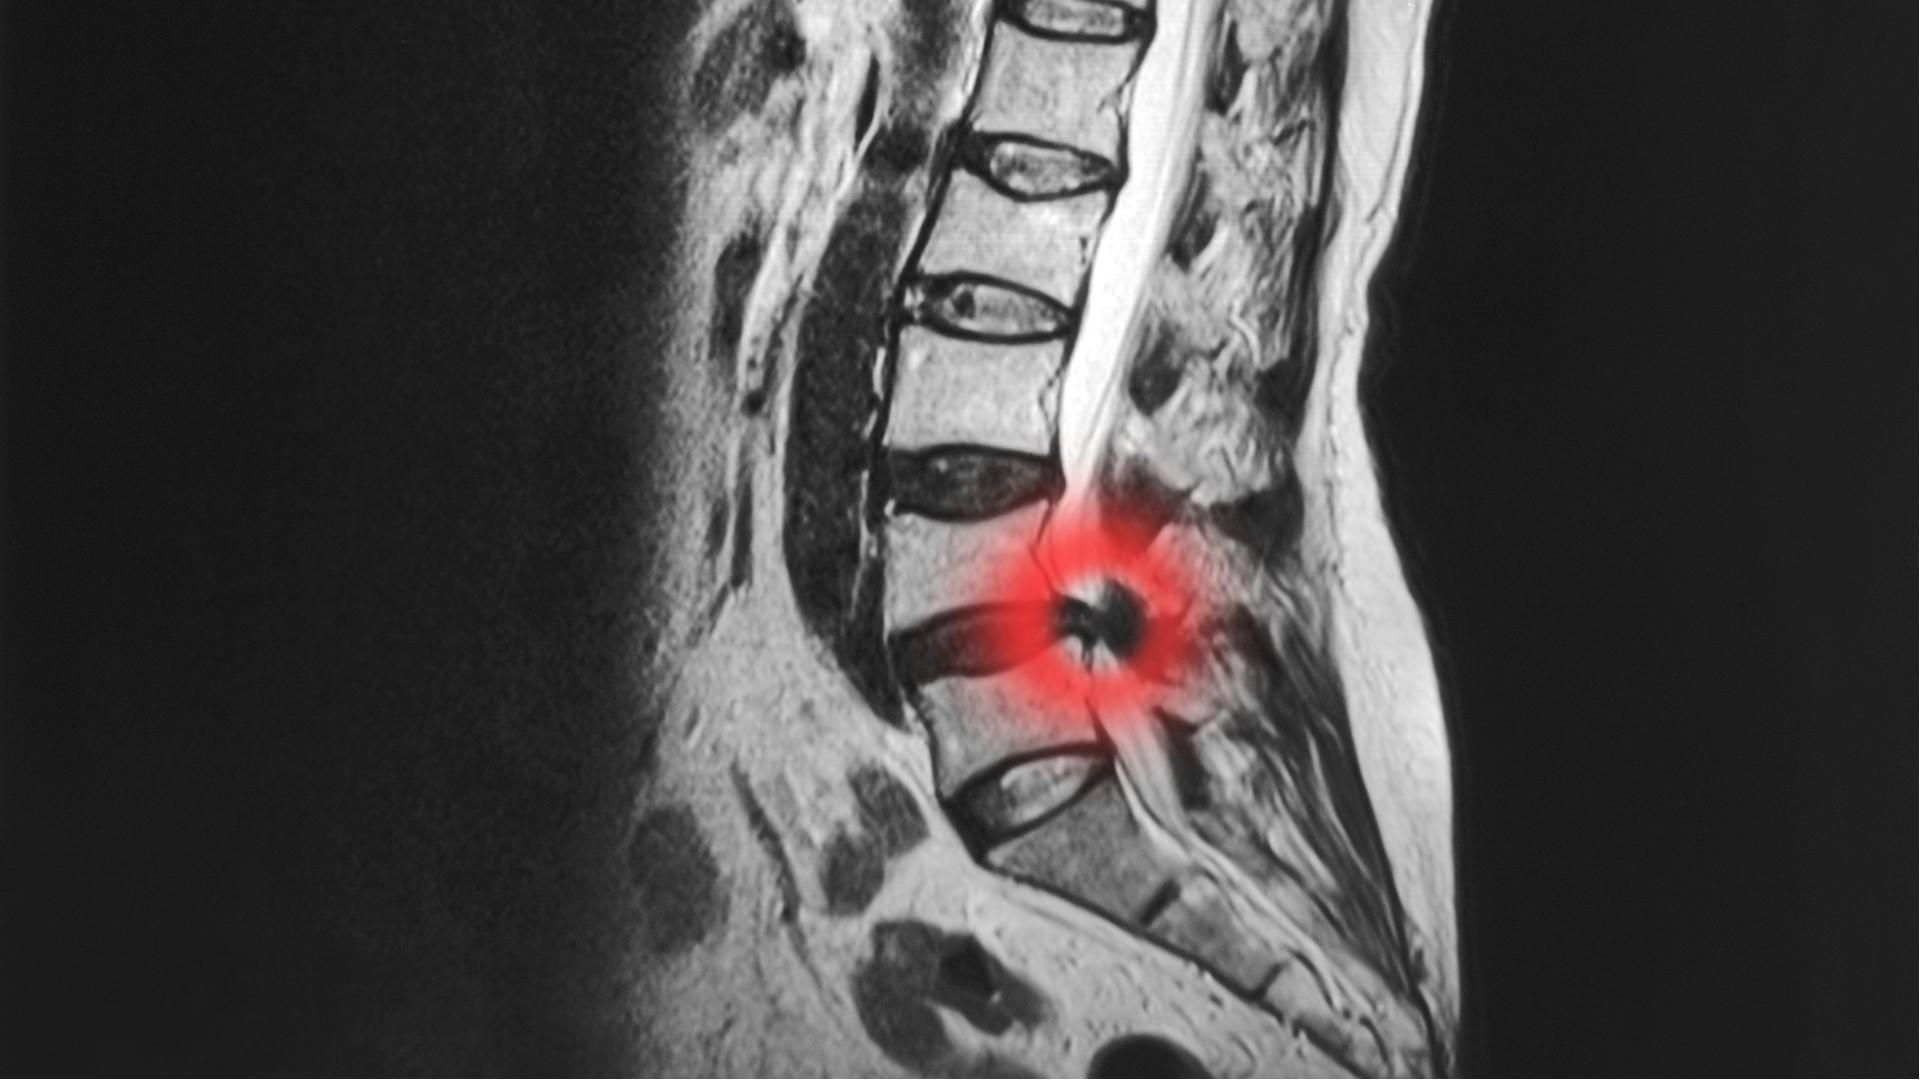

Sciatica is caused by inflammation around the root of the sciatic nerve, producing pain anywhere from the buttock all way down to the sole of the foot.

Sciatica can have many different causes, including:

• Trauma from lifting

• Disc Injury

• Muscular injury

• Restrictions in the joints around your low back or pelvis.

Sciatica and back pain can often be caused by trauma, commonly in the form of heavy lifting. The force of lifting a heavy object can cause damage to the outer casing of the disc, resulting in a sudden shape change, also known as a bulging or slipped disc, a common cause of sciatic pain.

Degeneration